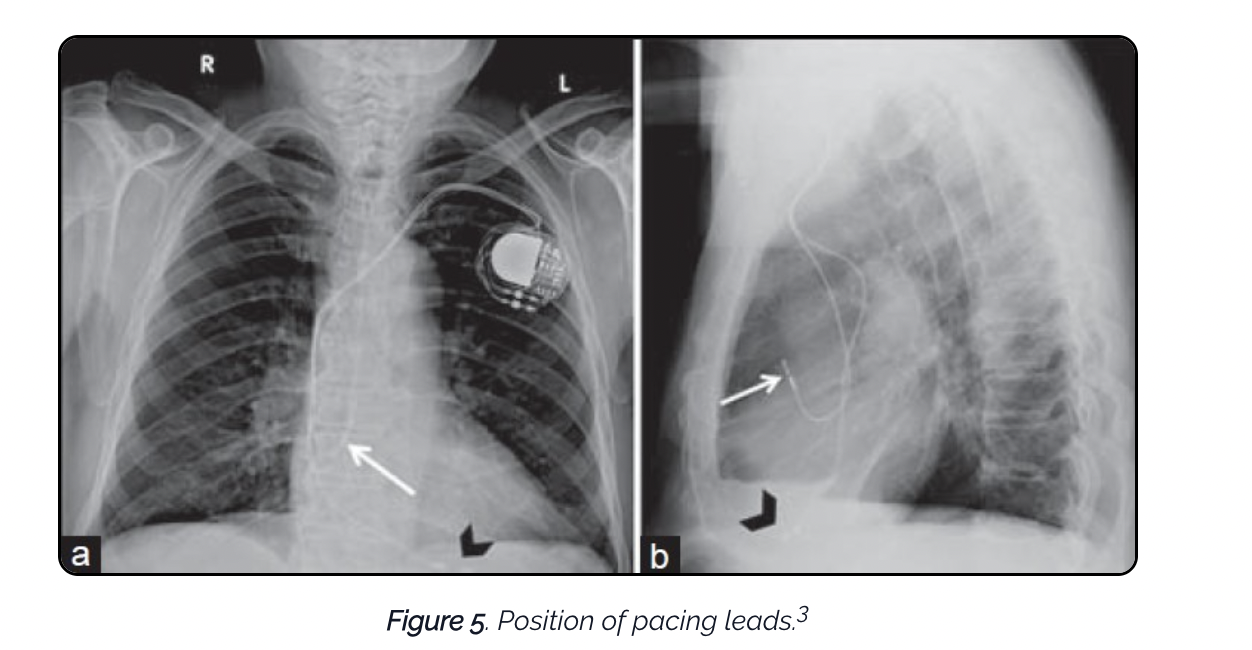

N.B. Right sided leads should be anteriorly located on lateral CXR